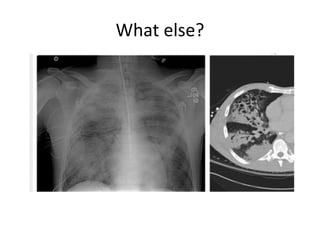

What else?

Post influenza pneumonia

Case 3 • 20yo previously healthy, one week of high fevers, chills, sweats, cough, multifocal rhonchi and rales • Influenza A positive • Treated with oseltamivir, CTX and azithromycin • No improvement in 4 days • Day 5: Persistent fevers 39.3, progressively hypoxic 2L NC to 50% FM in 24 hrs